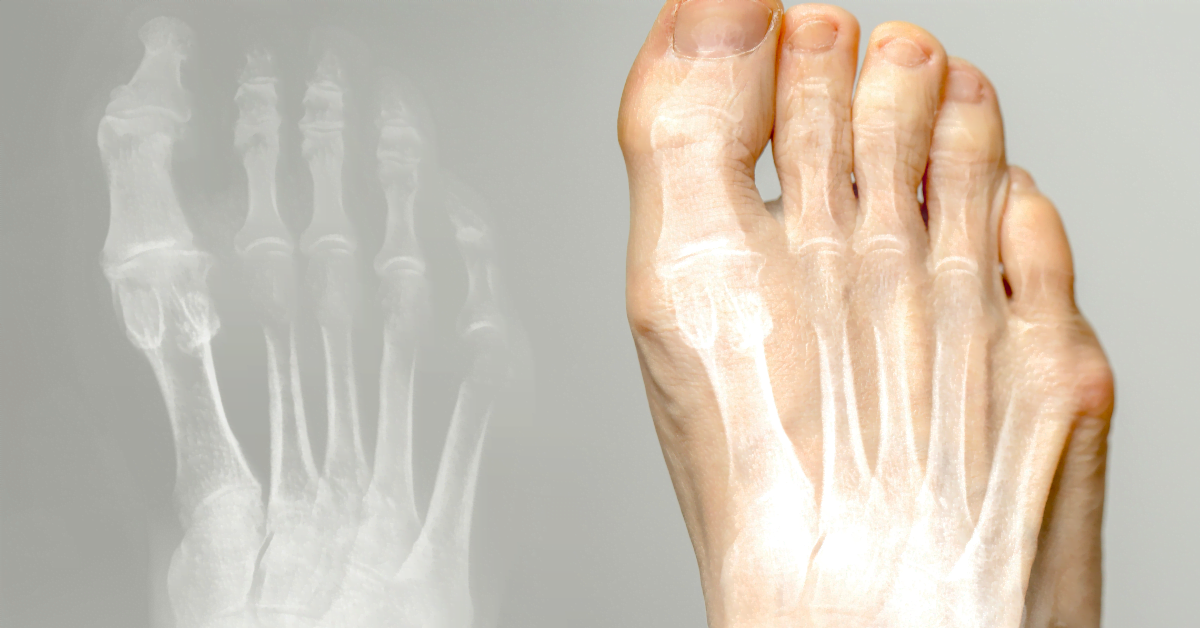

Hallux valgus (bunion) is a condition where the big toe points inward and forms a bump at the base. It can cause pain and discomfort. Here you can read about causes, treatment, and prevention.

The big toe bends towards the other toes, creating a foot bump. Causes: narrow shoes, high heels, heredity, flat feet or arthritis. Poor footwear causes pressure and friction, which can lead to bursitis.

Hallux valgus is a misalignment of the big toe inwards, with a bump at the base. Often due to narrow shoes, high heels, or heredity. Can cause pain and bursitis.